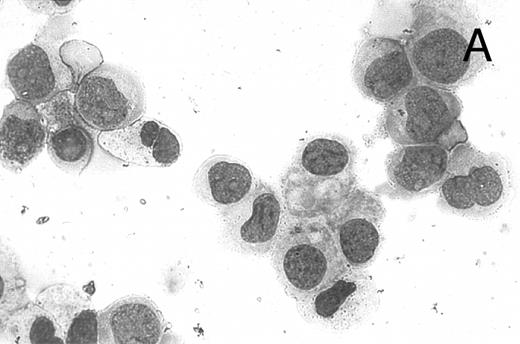

CD437 inhibition of HL-60R growth and induction of apoptosis.Although HL-60R cells are resistant to RA-mediated inhibition of growth,16,17 they are exquisitely sensitive to CD437-mediated inhibition of growth (Fig 1A) with as little as 25 nmol/L CD437 inhibiting growth by approximately 50% (Fig 1B). Similar inhibition of growth was noted in the parental HL-60 cell line (Fig 1C), as well as the RA-resistant K562 leukemia cell line28 (Fig 1D). As evidenced in Fig 1A, there was not only a total inhibition of cellular proliferation in the presence of CD437 but an actual cell loss. We therefore examined whether CD437 induced programmed cell death (apoptosis) in the HL-60R cells. That CD437 indeed induced apoptosis in the HL-60R cells was documented using three independent parameters. (A) HL-60R cells after exposure to 1 μmol/L CD437 displayed marked nuclear fragmentation and chromatin condensation, with the nuclear and cytoplasmic membranes remaining intact (Fig 2), a morphology indicative of apoptosis.29 (B) Incubation of HL-60R cells with 1 μmol/L CD437 resulted in internucleosomal cleavage and laddering of the DNA on gel electrophoresis (Fig 3), a hallmark of apoptosis.29 (C) A number of studies have suggested a critical role for cysteine proteases in the apoptotic process.30-37 Numerous substrates for this family of proteases have now been identified.37-41 PARP, which plays an important role in both DNA synthesis and repair, is cleaved early in the apoptotic process.37 38

CD437-induced apoptosis in HL-60R cells. HL-60R cells were grown as described in the Materials and Methods and exposed to either vehicle alone or CD437 (1 μmol/L) for 24 hours and then stained with aciridine orange. (A) Cells exposed to only vehicle. (B) Cells exposed to CD437 (1 μmol/L).